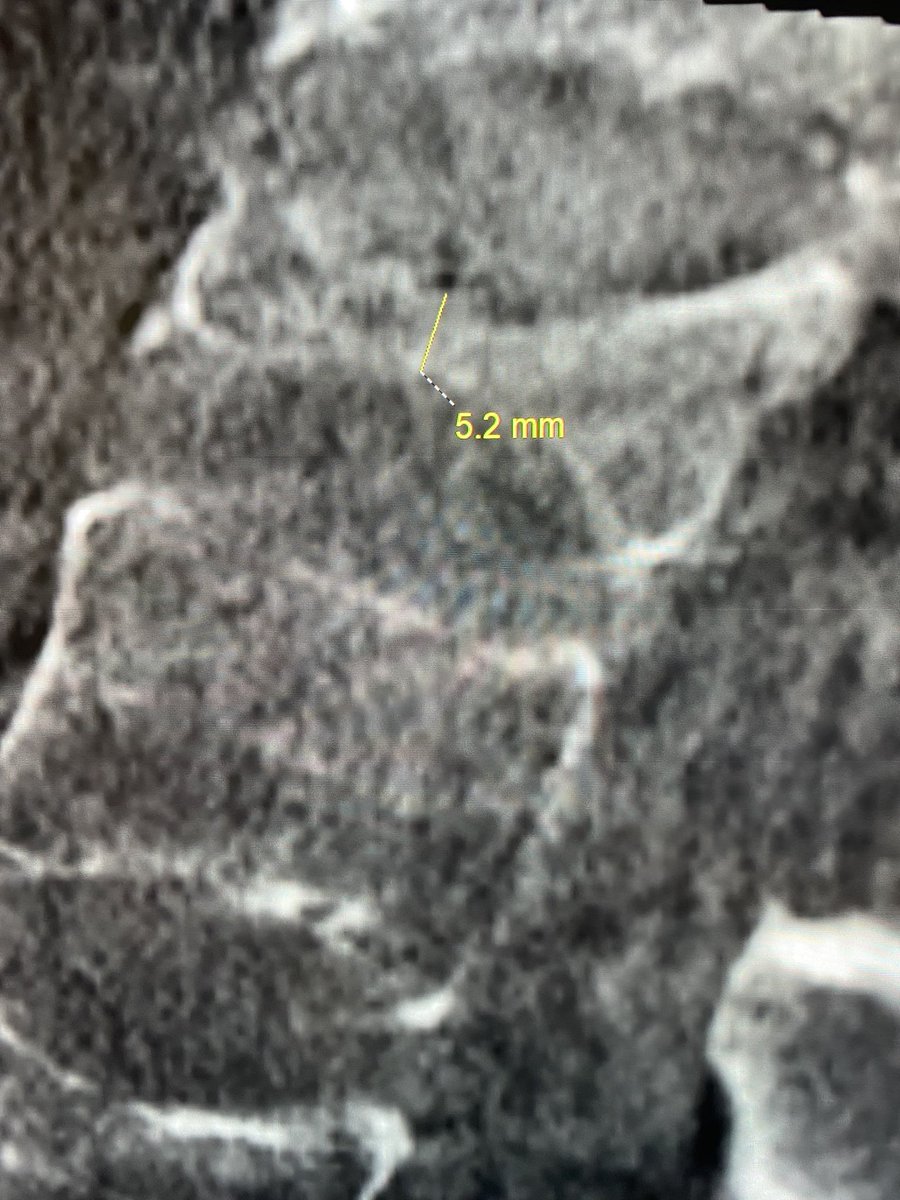

Please check out our new classification system for shunting AV lesions of the spine! We emphasis lesions with high risk features as these cause stroke and hemorrhage. A big thank you to @UCSF_NIR , @UCSFimaging , and @JNIS_BMJ.

Arteriovenous shunts of the cervical spine: patient demographics, presentation, patterns of high-risk venous drainage, and updated classification jnis.bmj.com/content/early/…